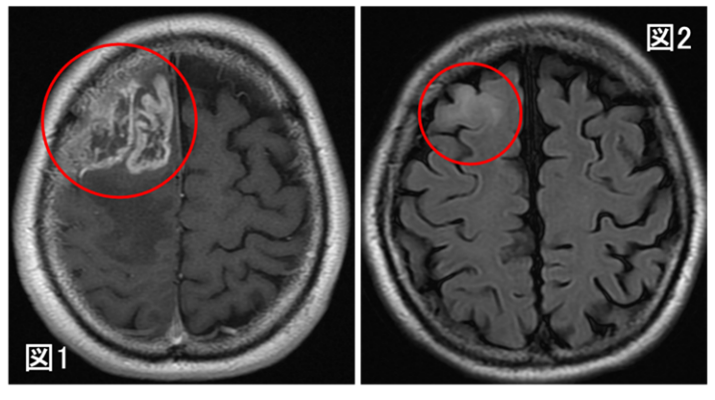

図1は膠芽腫の典型的な画像所見です。一般的にこのような画像所見を認めれば速やかな治療介入が行われるため、膠芽腫の自然歴を追うことは難しいとされています。しかし、こういった症例においても、過去に何かしら別の理由、例えば脳ドックや頭部外傷、別の脳疾患のフォロー目的などで頭部の画像検査をされていることがあるということに気づきました。その中には過去画像で何も病変がないものもあれば、膠芽腫の芽とも考えられるような微小な病変を認めるものもあり、こういった画像こそが膠芽腫の画像上の起源を推定できるデータになるのではないかと考えました。図2は図1と同一患者の画像ですが、7.5ヶ月前のものであり、微小ではありますが後方視的に見れば異常所見を認めています。